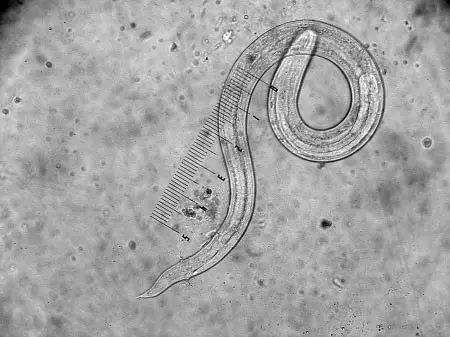

除了对农业生产的危害,福寿螺还对人类的健康造成了威胁。福寿螺是广州管圆线虫、卷棘口吸虫等寄生虫的中间宿主。2006年,北京有70多人因生食福寿螺引发了广州管圆线虫病,轰动全国,一时间人们谈“螺”色变。此后每年陆陆续续都有类似的报道。食用生的或未充分加热的福寿螺,可能引起广州管圆线虫等寄生虫在人体内感染,极易引起食源性广州管圆线虫病,感染此病,线虫幼虫会入侵人脑,损害中枢神经系统,引起嗜酸细胞增多性脑膜炎,可引起头痛、发热、颈部僵硬等症状,严重者可致痴呆,甚至死亡!